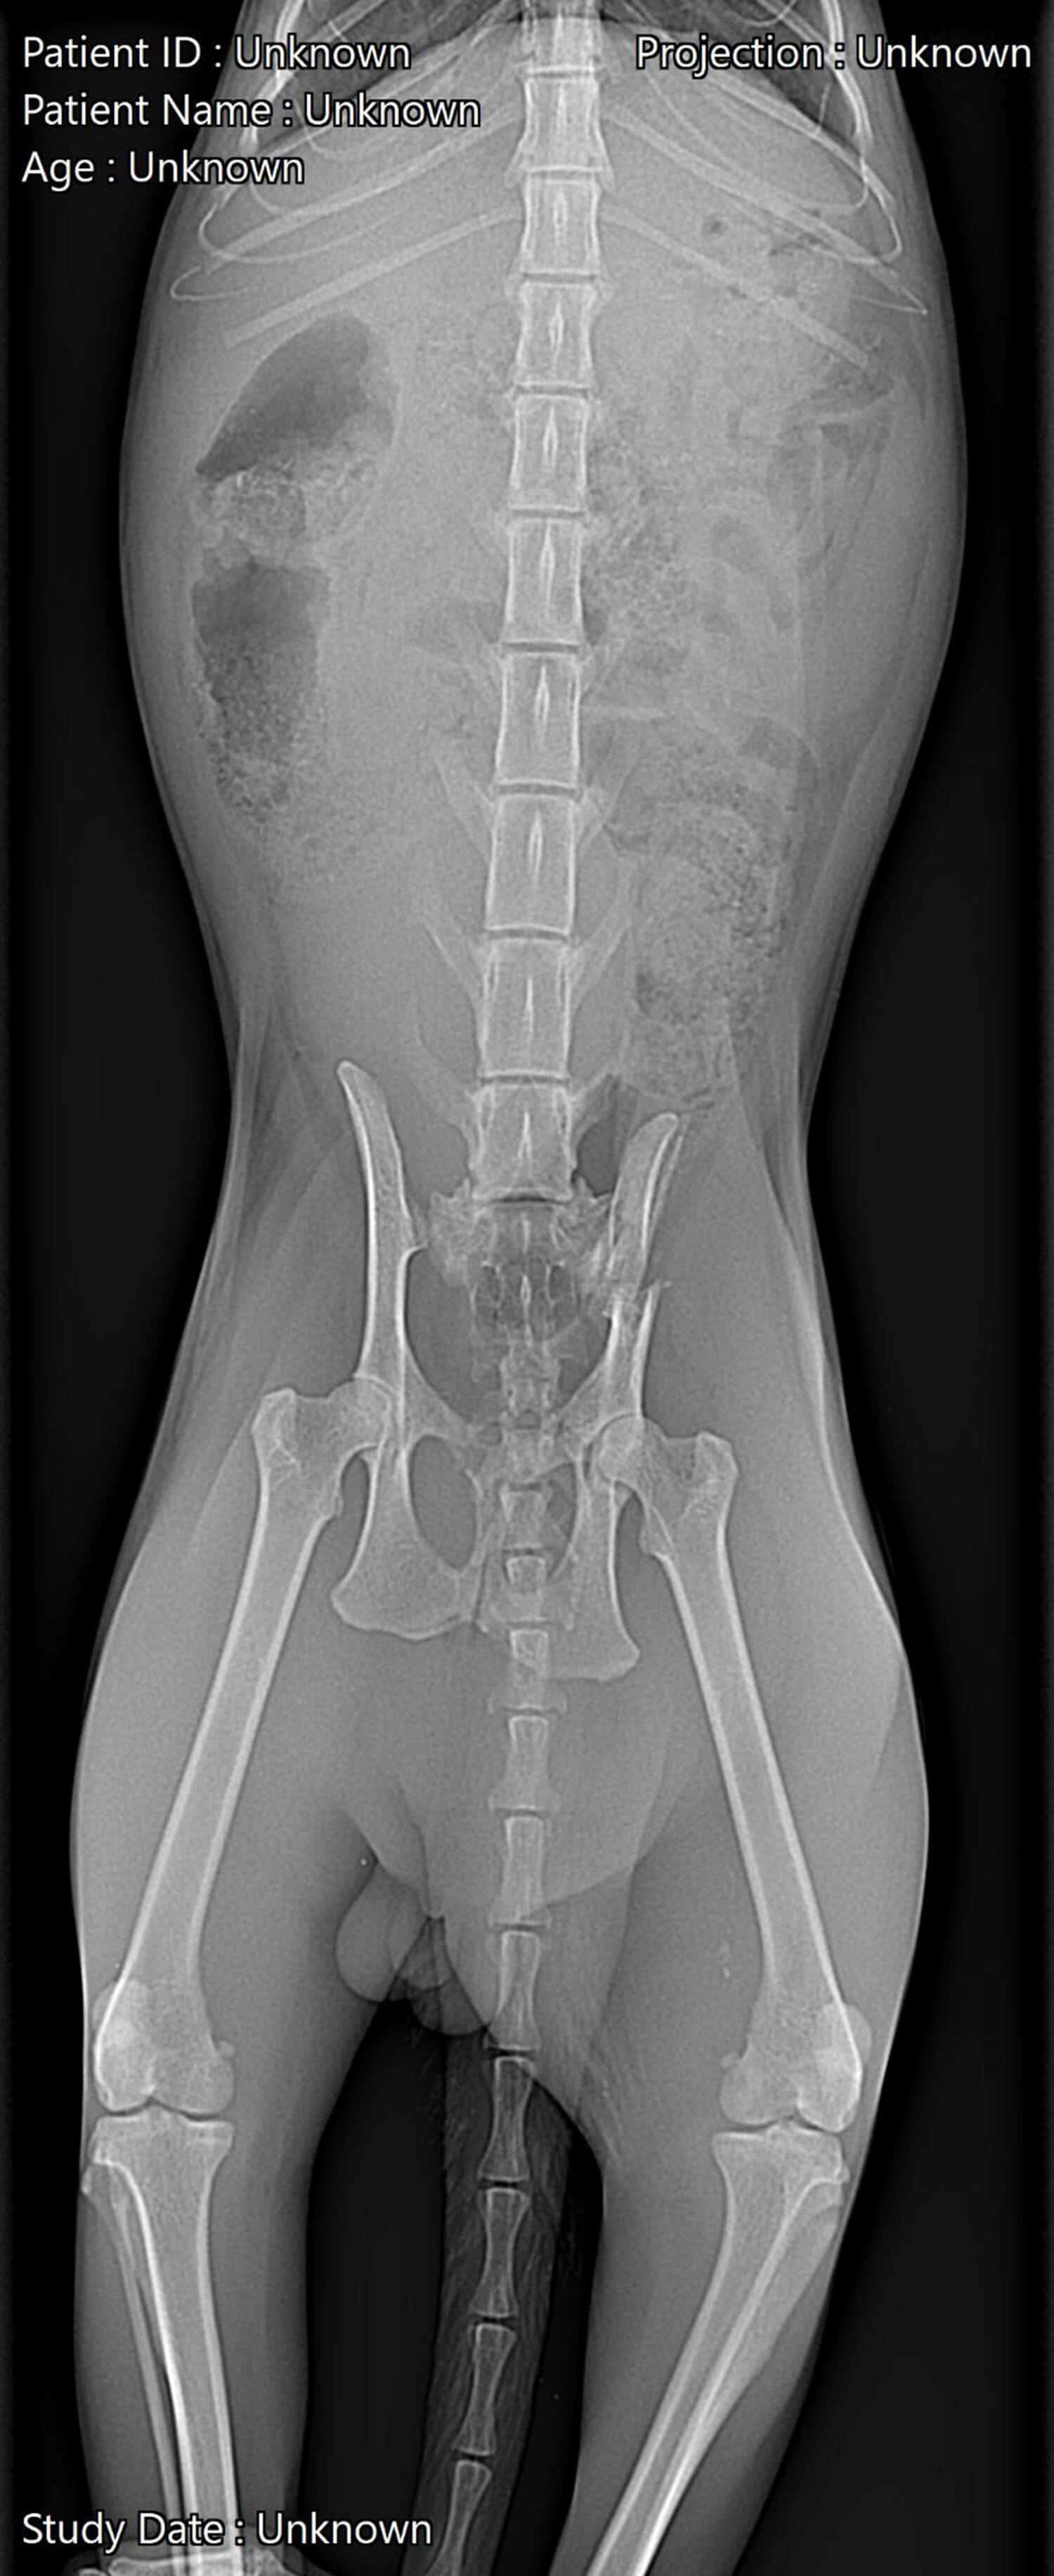

Ренгенови изследвания - дигитална рентгенография, контрастна рентгенография

Това е един от основните методи за изследване на много органи и системи. Златен стандарт за изследване на опорно-двигателният апарат. Използва се също и при  изследване на органите на пикочно - половата, храносмилателната система и на други коремни органи. Много удачен е при изследването на гръден кош.

Ветеринарната медицина вече има достъп до дигитални технологии, които значително подобряват качеството на ренгеновото изображение. Интерпретацията на снимки с много детайли и наслагвания на сенки изисква опит и систематичен подход при разглеждането им, за да не бъдат допускани грешки. Обикновено са необходими поне 2 снимки в 2 перпендикулярни равнини, но има и множество коси проекции. Допълнително може да бъде използвана и контрастна материя за по-добра визуализация при определени състояния.